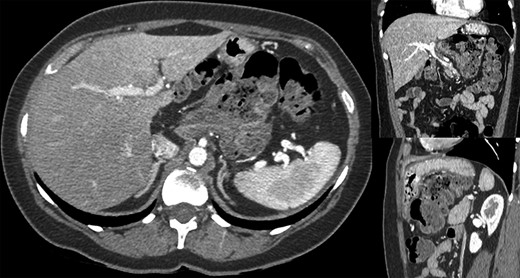

A 44-year-old female patient, without prior abdominal surgery, was admitted to the emergency department with an acute epigastric abdominal pain, without nausea. She presented similar episodes of pain in the past, without having ever requested a medical opinion. Physical examination revealed an acute epigastric pain without signs of peritonitis. Laboratory analyses were within normal limits. A computed tomography showed an internal hernia of the colon in the lesser sac, going back from the liver pedicle (Fig. 1). There were neither occlusion nor ischemia. We performed immediately a diagnostic laparoscopy with one 11-mm umbilical port and two 5-mm ports (one in the left lumbar and one in the hypogastrium). Exploration confirmed that the ascending colon and the right colonic flexure had herniated through the foramen of Winslow (Fig. 2). The colon was reduced with an atraumatic Johann’s graspers and was viable, cecum, ascending colon and the right colonic flexure was mobile due to a misapposition of the right Told fascia. To prevent recurrent herniation we performed the fixation to the lateral wall of the cecum, ascending colon and right colonic flexure with several non-absorbable sutures (Fig. 3). We did not perform the closure of the Winslow’s hiatus. Postoperatively, the patient recovery was uneventful and was discharged home 2 days later. A computed tomography was performed 1 month later for another reason, showing a good result of the right colon fixation on the lateral wall (Fig. 4). Twenty months after surgery, the patient totally recovered and has not experienced any recurrence or occlusion.

Computed tomography showed an internal hernia of the colon in the lesser sac, going back from the liver pedicle.